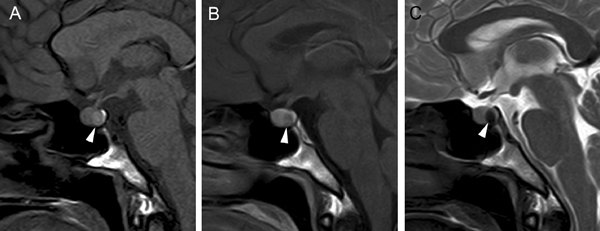

Figura 2A y B. Cortes sagitales de RM y TAC. Adenoma pituitario con invasión del esfenoides y del clivus (puntas de flecha). Es posible demostrar las estructuras óseas en RM con similar precisión que la TAC.

Figura 12A. Microadenoma pituitario (8 mm), corte coronal, secuencia convencional T1w con Gadolinio, el tumor lateralizado a derecha, erosiona y deforma el piso de la silla turca (punta de flecha). B. Mismo paciente, 3 meses post-tratamiento médico, corte coronal secuencia T1w con Gadolinio, El tumor ha modificado su forma, se ha reducido de tamaño (punta de flecha) y la glándula muestra ahora un borde superior cóncavo, con una pequeña herniación de la cisterna supraselar. Los macroadenomas pituitarios producen expansión de la silla turca, con moderado refuerzo del tumor después de la inyección de gadolinio. La densidad (TAC), intensidad de señal (RM) y características del refuerzo con medio de contraste yodado (TAC) o gadolinio (RM) no son específicas, pero el aumento de volumen y erosión de la silla turca, la invasión del seno cavernoso y la presencia de contornos lobulados (64%) son hallazgos frecuentes en un macroadenoma42-44. El aumento de volumen selar se observa en 94 a 100% y la erosión de las paredes de la silla turca, incluyendo el piso selar, dorso selar, tubérculo selar y extensión al seno esfenoidal, está presente en 76% de los macroadenomas. La invasión del hueso esfenoides y del clivus (Figura 2Ay 2B) se demuestra en 19% de los casos.